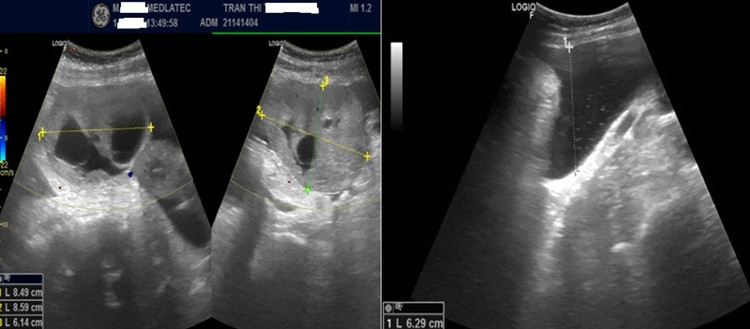

Kết quả, xét nghiệm dấu ấn ung thư thấy nồng độ CA 125 tăng cao ở mức 399 U/mL (giá trị bình thường 0–35) và HE4 là 469 pmol/L (bình thường <60,5). Siêu âm ghi nhận, hình ảnh khối hỗn hợp âm vùng tiểu khung, theo dõi u buồng trứng trái kèm dịch tự do ổ bụng.

Hình ảnh siêu âm ổ bụng của bệnh nhân/Ảnh Medlatec